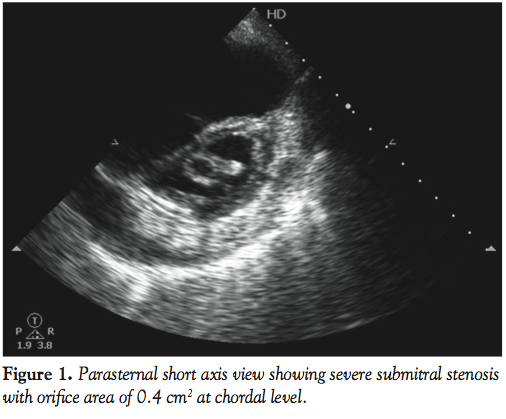

The coiled guidewire was withdrawn and a 0.035-inch Terumo wire (Terumo Corporation) was introduced into LV with the support of a Judkins right catheter (Figure 5) and the distal end was parked in the right subclavian artery. An 8 x 20 mm Opta-Pro PTA balloon (Cordis Corporation) was passed over the Terumo wire and the submitral apparatus was serially dilated (Figure 6). The Terumo wire was then exchanged for a coiled guidewire and the procedure was completed with a BMV balloon catheter (Figure 7). The medial commissure was split (Figure 8) and the submitral stenosis was released (Figure 9).